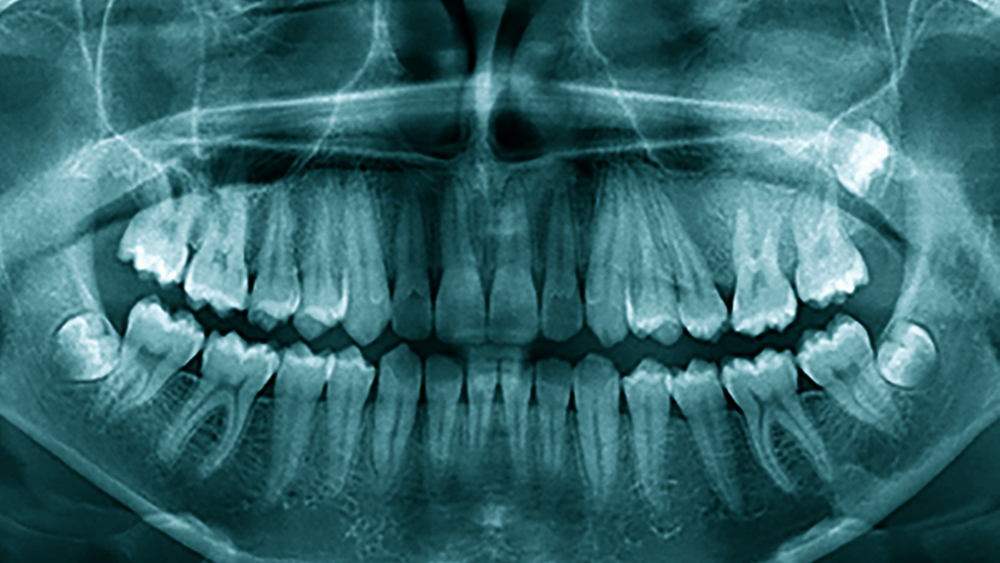

Im Orthopantomogramm (OPG) von 2020 (Abbildung 1) zeigte sich eine Divergenz zwischen den Zahnwurzeln 25 und 26 bei interdentaler homogener Verschattung mit Ausdehnung innerhalb des Processus alveolaris der Maxilla in Höhe 25 bis 27 sowie Fortsetzung nach kranial mit Projektion auf den Sinus maxillaris links. Nebenbefundlich waren die Weisheitszähne 28, 38 und 48 raumbeengt angelegt. Im OPG von 2017 (Abbildung 2) hatte schon eine angedeutete Divergenz der Wurzeln 25 und 26 ohne weitere Hinweise auf das sich später entwickelnde Bild bestanden, möglicherweise der Punkt, von dem die Erkrankung ihren Ausgang nahm. Hauszahnärztlich waren Erkrankungen der Zähne und des Parodonts im Vorfeld ausgeschlossen worden.